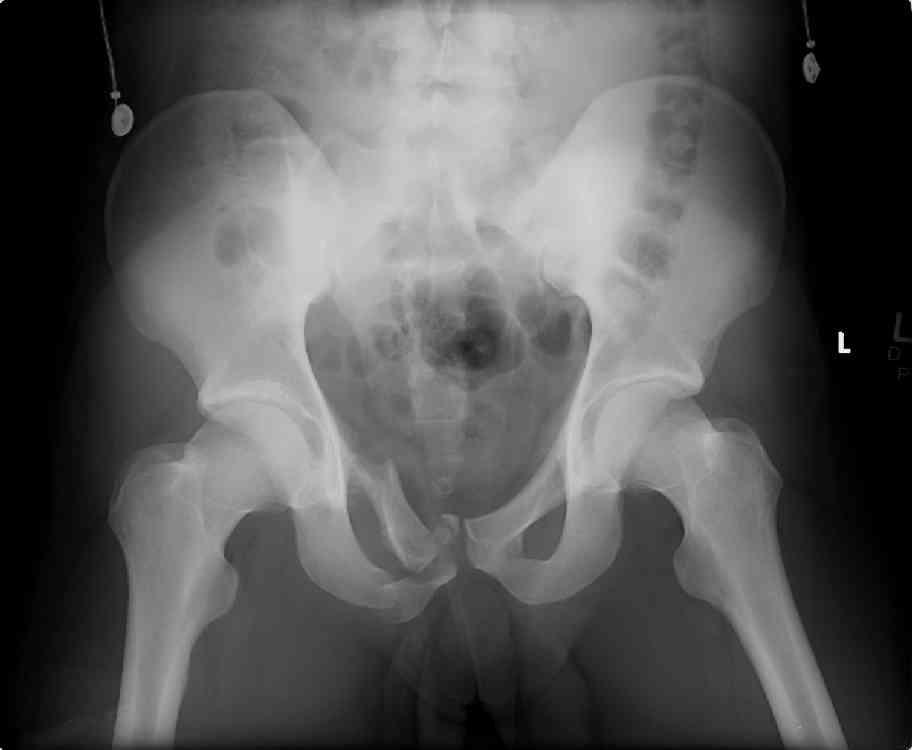

hello,this is a healthy 22yo male. peds vs auto.

no other injuries. has anyone treated these non-operatively? thanks.

It's type A pelvic-ring lesions. Because

the pelvic ring is stable, it

cannot be displaced by physiologic

forces and may be treated non-operativly in male.

One bit of important yet omitted info is the patient's physical exam... if this pelvic ring injury is unstable to exam, then I'd recommend operative reduction and stable fixation to him.